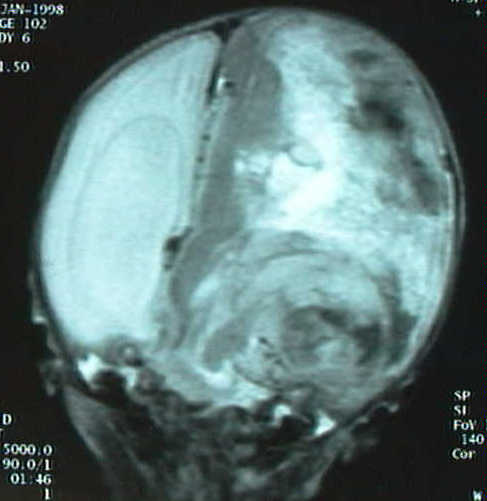

En controles ecográficos y por tomografia computada posteriores (fig. 1a-b) se constata necrosis tumoral, dilatación de vena cava superior y shunt derecha-izquierda a nivel del ductus arteriosus; clínicamente se detecta proptosis izquierda, hipotensión, reborde hepático, e hiperbilirrubinemia que precisa fototerapia. Se practican estudios por Resonancia Magnética para estudio de extensión e intentar caracterizar la masa (fig 2a-c).

Figura 2 (a,b,c): Imagen por Resonancia Magnética. En los cortes parasagital derecho (a) e izquierdo (b) se observa una gran hidrocefalia, herniación transtentorial, aplanamiento del cerebelo y distorsión del tronco y 4º ventrículo. En el corte coronal (c) se observa desplazamiento de la línea media por una gran masa tumoral con marcada heterogeneidad, e imágenes sólidas y quísticas, estas últimas sugestivas de necrosis extensa